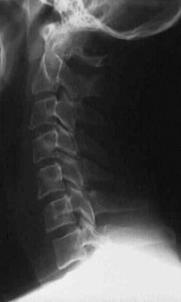

TRAUMA CERVICALA

Incidenta laterala Incidenta

laterala Incidenta

antero-posterioara

Aspect normal Imagine

incompleta Aspect

normal